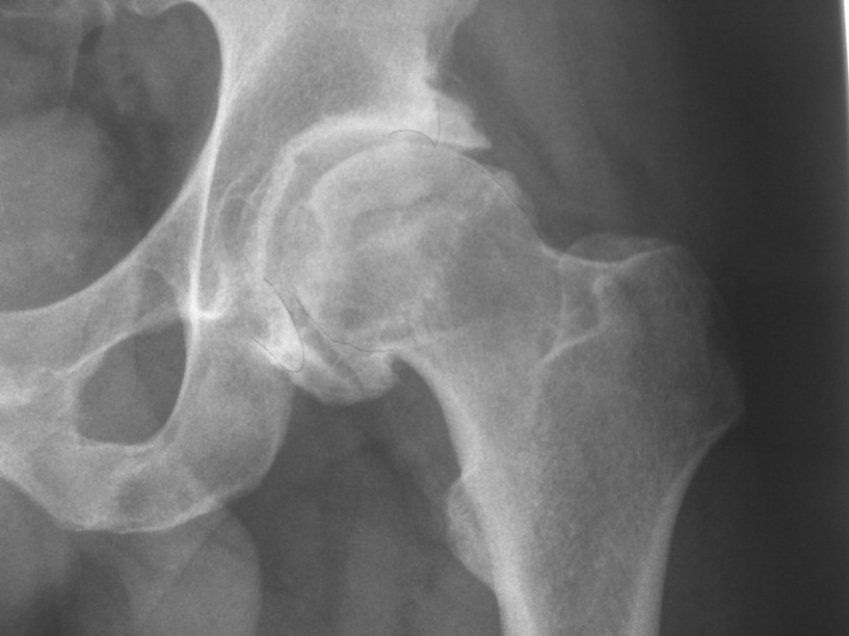

La Artrosis es una enfermedad degenerativa de las articulaciones. Consiste en la pérdida del cartílago articular, la formación de osteofitos y la deformación de la articulación afectada. Existen factores desencadenantes, como un traumatismo importante, y factores que aceleran la progresión de la artrosis, como la inestabilidad o la sobrecarga mecánica de la articulación. También existe una predisposición genética a padecer la enfermedad. La artrosis es habitual en articulaciones como la rodilla, la cadera, las articulaciones de las manos y la columna vertebral.

La artrosis de cadera es frecuente. Puede ser primaria o secundaria a diversas patologías. Entre las más frecuentes están la Luxación traumática de la cadera, la Necrosis avascular de la cabeza del fémur, las Epifisiolisis de la cabeza del fémur, la Enfermedad de Perthes o la Displasia del desarrollo de la cadera.

La artrosis de cadera se caracteriza por el dolor en relación con la actividad, sobre todo en la región inguinal, y la disminución de la movilidad de la misma. Además pueden existir crujidos y pérdida de fuerza en la pierna. Si es avanzada es habitual la cojera.